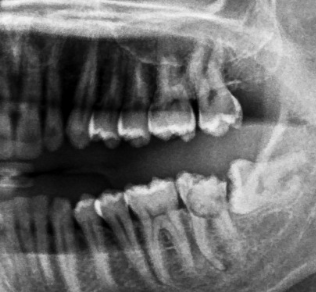

Ok, now let’s see my teeth after did some x-ray in one of hospital in Cibubur area.

teeth x-ray

You see, my tooth number 38 has a malposition! πŸ˜… The angle has 90 degrees! that’s bad! And my tooth number 37 has a BIG hole, those 2 teeth will not be able to be maintained anymore 😩. The root cause of the pain here is only 2 teeth, which number 37 and 38!.